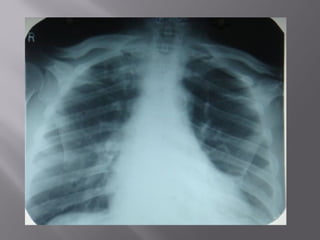

 7. Rotation

 Medial ends of

bilateral clavicles are

equidistant from the

midline or vertebral

bodies

 7. Rotation Medial ends of bilateral clavicles are equidistant from the midline or vertebral bodies